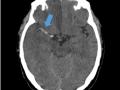

| Conceito importante: a transudação ependimária é um tipo de edema cerebral que ocorre quando há aumento da pressão intraventricular caracterizada pelo rompimento do revestimento ependimal ventricular permitindo a migração de fluído cefaloraquidiano para o parênquima cerebral adjacente aos ventrículos. Normalmente é observada nos ao redor dos ventrículos laterais no contexto de hidrocefalia obstrutiva aguda. Na tomografia é notada como hipoatenuação na região periventricular com apagamento dos sulcos corticais adjacentes, além das alterações relacionados com hidrocefalia. |

| Corte axial de tomografia computadorizada mostrando hidrocefalia com sinais de transudação ependimária adjacente aos ventrículos laterais, notadamente no corno frontal direito. |